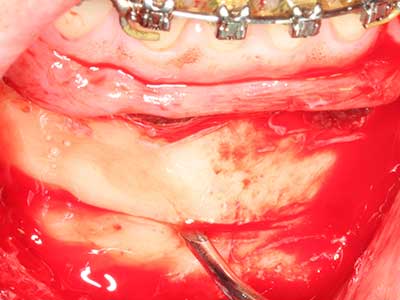

Fig. 18: Preparación de una tapa cortical con la sierra ósea piezoeléctrica (Piezomed, W&H).

Fig. 19: Zona operada después de neurolisis y eliminación del osteomo.

Fig. 20: La tapa ósea extraída se readapta y se fija mediante un tornillo para osteosíntesis (KLS Martin, Tuttlingen).